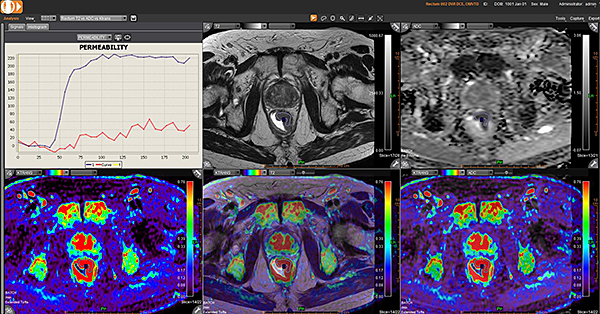

Додаток Prostate Streamlined.

Спеціальні програми Olea SphereTM для аналізу передміхурової залози включають в себе розширені можливості для оцінки дифузії та якісної оцінки перфузії. Також пропонують ефективний мультипараметричний аналіз усіх доступних послідовностей для візуалізації простати. В додатках реалізовано аналіз кінетики та кількісних даних на основі надійних математичних моделей. Програми передміхурової залози включають звіт PI-RADS® 2 для покращення виявлення, характеристики та вірогідності встановлення діагнозу раку простати. Цей програмний пакет стандартизує виклад протоколів опису, а також вказує рівень підозри або ризик виникнення клінічно значущих пухлин.

Додаток MR Prostate

Додаток MR Prostate інтегровано до розширеної візуалізації Vitrea. Він забезпечує виявлення, характеристику та стадіювання ураження.

Забезпечує миттєву комплексну оцінку ураження та високоякісну оцінку дифузії

Дає змістовну звітність, включаючи локалізацію та об’єм ураження

Надає рекомендації PI-RADS V2 щодо стандартизації термінології і протоколу опису, а також уточнює ризик клінічно значущих пухлин